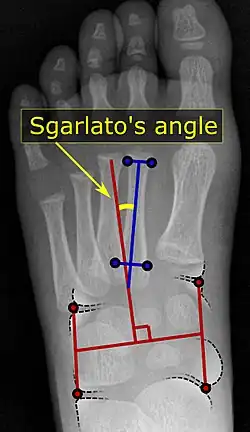

A Sgarlato's angle of more than 15° indicates pigeon toe.[9]

Pigeon toe can be diagnosed by physical examination alone.[10] This can classify the deformity into "flexible", when the foot can be straightened by hand, or otherwise "nonflexible".[10] Still, X-rays are often done in the case of nonflexible pigeon toe.[10] On X-ray, the severity of the condition can be measured with a "metatarsus adductus angle", which is the angle between the directions of the metatarsal bones, as compared to the lesser tarsus (the cuneiforms, the cuboid and the navicular bone).[11] Many variants of this measurement exist, but Sgarlato's angle has been found to at least have favorable correlation with other measurements.[12] Sgarlato's angle is defined as the angle between:[9][13]

• A line through the longitudinal axis of the second metatarsal bone.

• The longitudinal axis of the lesser tarsal bones. For this purpose, one line is drawn between the lateral limits of the fourth tarsometatarsal joint and the calcaneocuboid joint, and another line is drawn between the medial limits of the talonavicular joint and the 1st tarsometatarsal joint. The transverse axis is defined as going through the middle of those lines, and hence the longitudinal axis is perpendicular to this axis.

This angle is normally up to 15°, and an increased angle indicates pigeon toe.[9] Yet, it becomes more difficult to infer the locations of the joints in younger children due to incomplete ossification of the bones, especially when younger than 3–4 years.